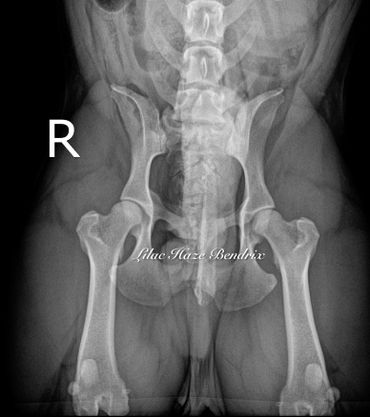

GRCH Lilac Haze Bendrix Hip Radiograph and OFA Certificate EXCELLENT Hips

OFA Certifications for Ch. Lilac Haze Bendrix; Excellent Rated Hips

GrCH Lilac Haze Bendrix OFA CHIC #149941 EXCELLENT Hips

There's more to Benny than meets the eye. While the color is beautiful, there is a great dog behind the amber eyes. Not only does he have proven structure and conformation in the show ring (as do his Champion and Grand Champion offspring Ch. Crowd Pleazer's Firecracker GiGi and GrCh. Peerless Hannibal at the Gates), but most importantly he's extensively health tested with multiple OFA certifications that include an extremely RARE rating of EXCELLENT Hips.

To put that in context, there are only 96 French Bulldogs in the 23-year history of OFA testing* that have ever received that hip rating, and only 15 male French Bulldogs under age 5.

Benny is one of only 1008 French Bulldogs to have a CHIC Certification. Of those FBDs, only 29 male FBDs (2.8%) have ever been CHIC certified with the EXCELLENT rating in over 23 years of testing.